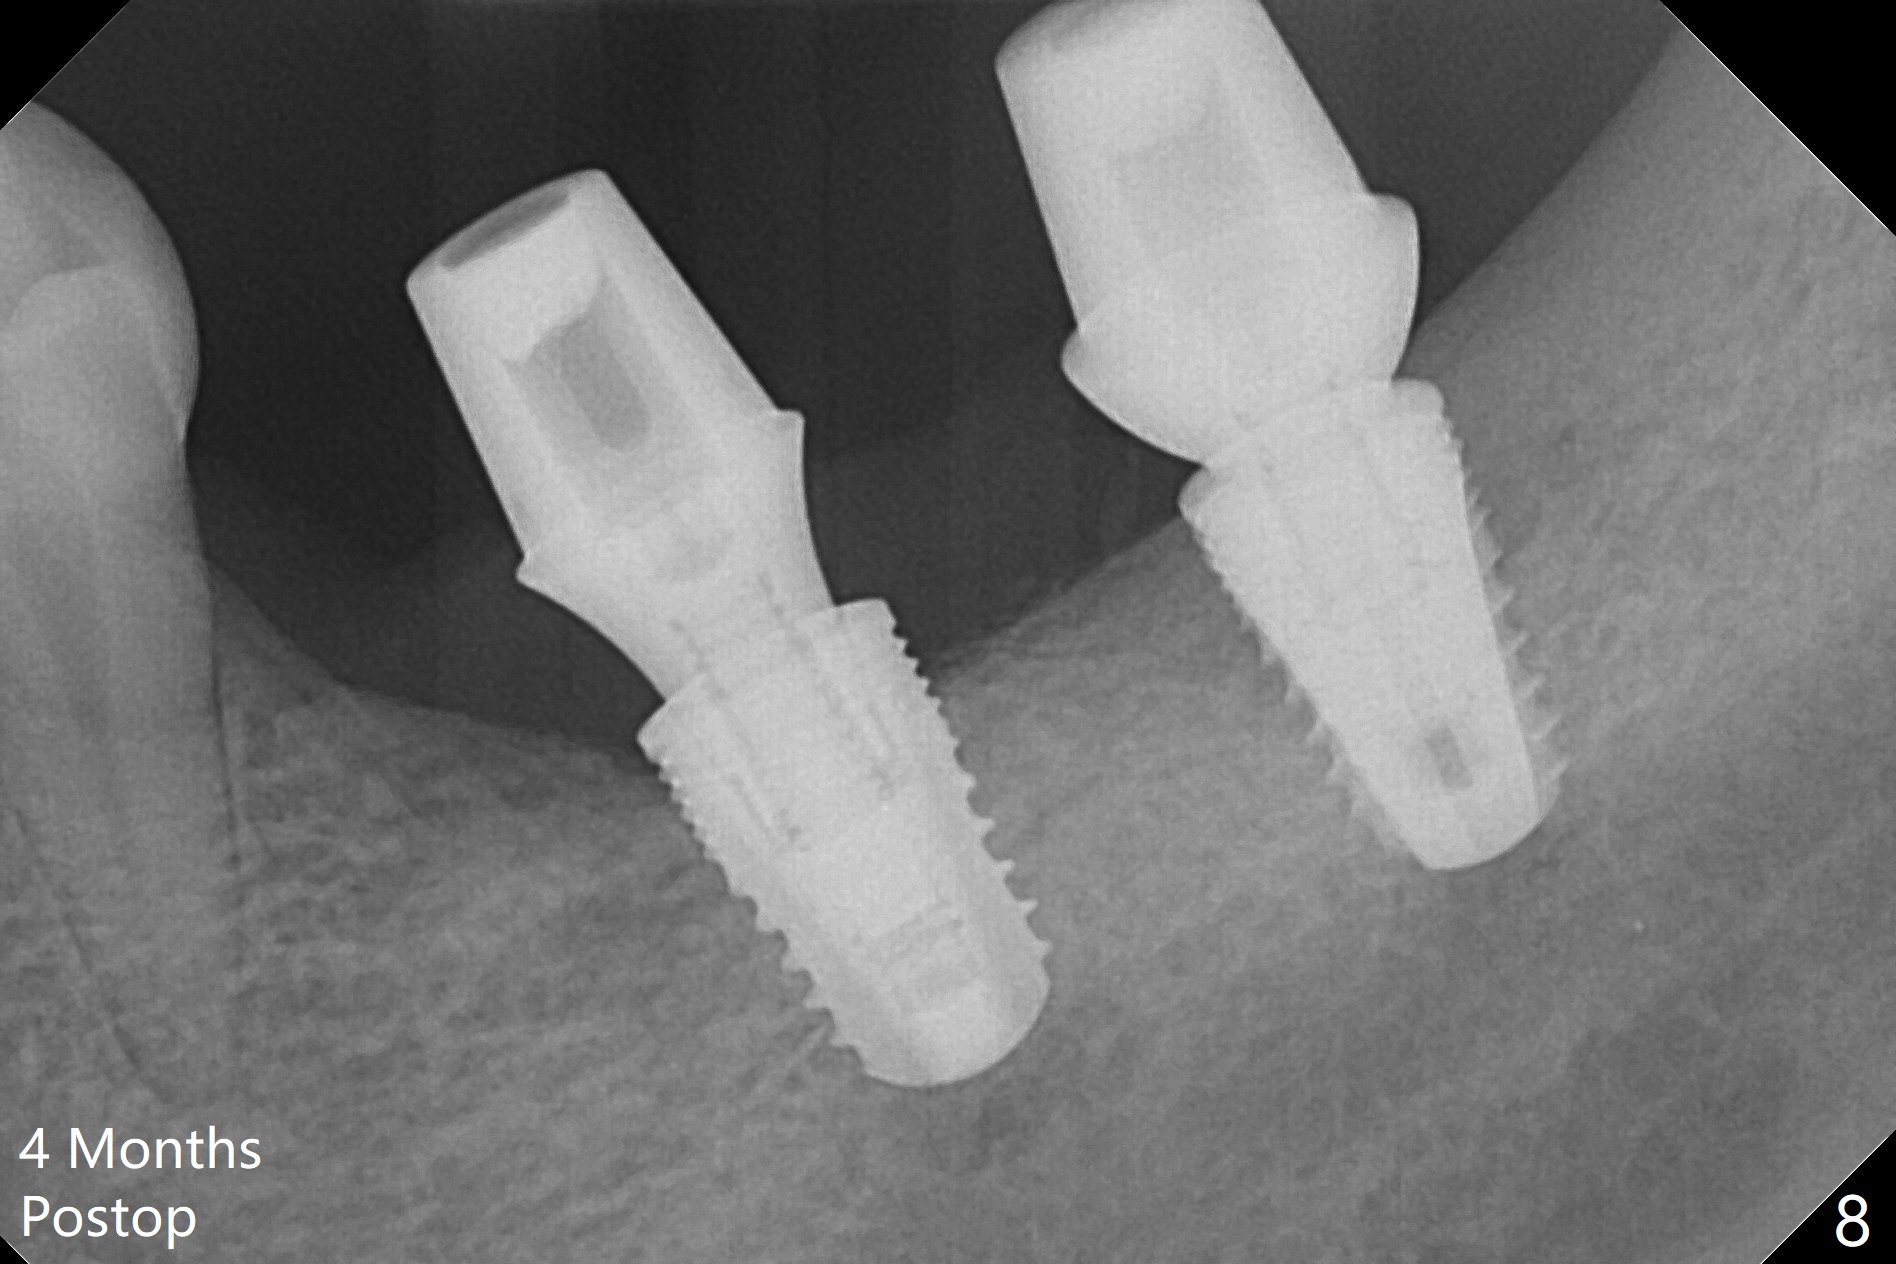

Preop photo shows severe mesial tilt of the tooth #18 (Fig.1). After extraction, the osteotomy is established in the apical end of the socket, where the buccolingual width is limited. It appears that an extra wide implant (5.9 mm) may perforate one of buccolingual plates. On the other hand, the buccal plate (Fig.2 double arrows) is intact and approximately 2 mm tall, whereas the lingual one is thin and lower. Initial osteotomy confirms that bone heights at #18 and 19 are 6 and 8 mm, respectively. Counting 2 mm of the buccal plate and bone graft lingually, a 8 mm long implant may be a practical option at the site of #18. After initial placement of two of 5x8 mm SM implants (Fig.3), the depth of the implant at #19 is adjusted twice (Fig.4,5). With placement of autogenous and allograft (Vanilla, Fig.5 *)) and abutments, a piece of cotton pellet is placed in each abutment well (access, Fig.6 *). Periodontal dressing is applied to the abutment wells for additional retention (Fig.7 *). Due to local poor oral hygiene, splinted provisional is fabricated 4 months postop (Fig.8) in preparation for limited orthodontic uprighting the tooth #20. The patient has pain with mastication at #18 eleven months post cementation (Fig.9). It appears that both of the implants should be removed with immediate replacement and bone graft. Prepare 4 PRF and sticky bone. The new implant will be 5.0 or 5.5x5 mm (Fig.10 green) with 2.3 mm platform (white). A block graft will be harvested from the ipsilateral ramus using 9/8 and 6/5 mm trephine burs for 2-3 mm in depth (Fig.11 blue). The ring graft will be seated around the platform over the implant (Fig.12).